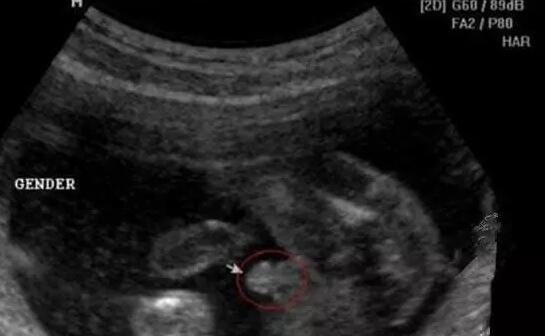

男宝宝如何通过B超分辨出来呢,其实也很简单了,如果角度合适,男宝的B超图上是可以看到小丁丁的。下图拍摄取的角度就是宝宝屁屁正下方,一目了然。

小丁丁